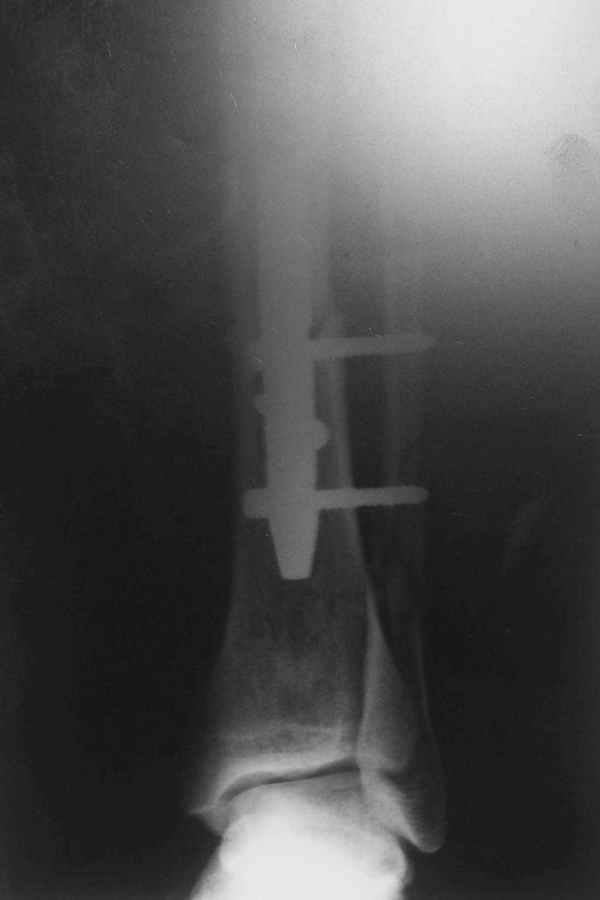

Не удается отправить первичные снимки. А что скажите по имеющимся?!

Выполненный остосинтез нестабилен. Штифт надо заменить по "размеру" на солидный, дистльно три запирающих винта. Успехов!

Перелом спиральный, то есть низкоэнергетический, так что со сращением дело обстоит уже неплохо, лишь бы "костоеда" не развилась. Отломки выглядят уже стабилизированными костной мозолью, так что довводить винты, наверно, уже незачем. Разве что при клинической оценке подвижность еще есть - тогда можно для стабилизации наложить простейший аппарат, не опасаясь контакта его элементов с гвоздем, поскольку места в дистальном метафизе оставлено более чем достаточно.

С Александром согласен, нет необходимости делать дополнительные усилия для сращения, не большая компрессия аппаратом из двух колец и полная нагрузка доделает работу.

Потекли блокирующие винты.

Удалять их всё равно придётся.

Уже имеется какое-то сращение. А в этих условиях выполнить реостеосинтез гвоздём не дольше, чем "накинуть" аппарат из двух колец. Ходить можно сразу с полной нагрузкой, да и качество жизни пациента без аппарата лучше.